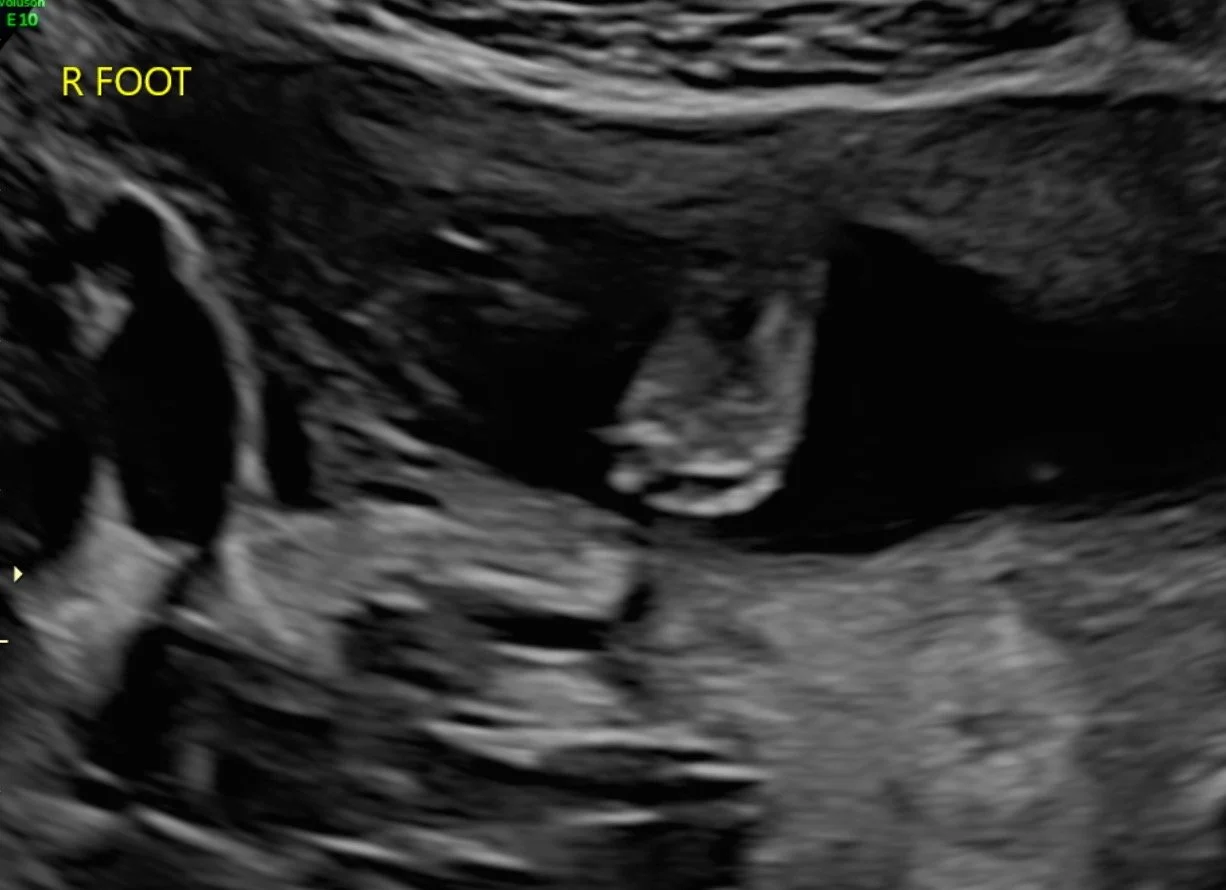

My ultrasound at Mount Sinai Hospital — it was on a large screen above me, and I got to watch everything being done. My doctor was exceptionally thorough and explained everything. Look at our little sweetie!